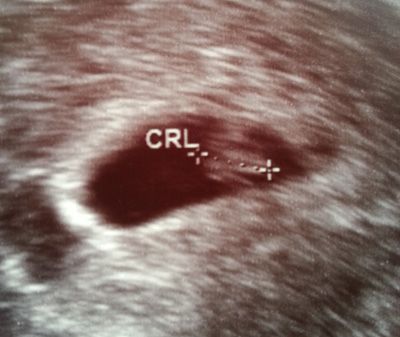

Tallah Skrevet 26. oktober 2014 #3 Skrevet 26. oktober 2014 Her er mitt UL-bilde fra uke 6+5 Vi så en tydelig spire med hjerteslag. Den ble målt, så det var plommesekk der og at spiren generelt var på riktig sted inni der. Mange sier man ikke ser så mye, men det man ser er virkelig alt man trenger på dette tidspunktet ♥

Paeonia Skrevet 26. oktober 2014 #5 Skrevet 26. oktober 2014 Vi var på ultralyd på torsdag, da var jeg ca 7+5. Vi så det lille knøttet vårt, ca 1,4 cm lang og med et bittelite hjerte som jobba som en helt Vi kunne også se ryggraden godt fra en av vinklene, også hode og noe som jeg regner med var bena. Plommesekken så vi også. Her er link til bilde: https://imageshack.com/i/eyPWrMqKj